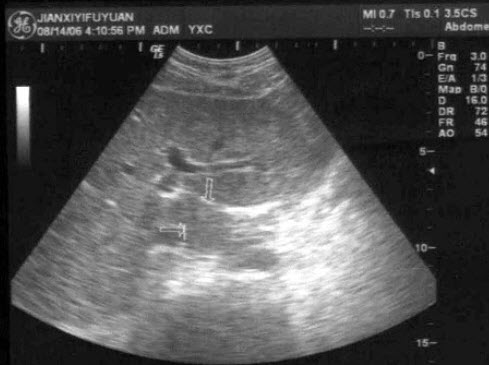

46、单项选择题

患者,消瘦,于左上腹触及一包块,超声见一大小5×7cm的呈假肾征的光团,如图所示,考虑为()

A.胰腺癌

B.胆囊癌

C.肝癌

D.胃癌

E.左肾癌